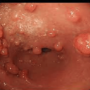

Данное заболевание имеет несколько видов. Простой баланопостит вызывает покраснение и воспаление крайней плоти и головки полового члена, появление отека, с дальнейшим формированием на слизистой болезненных язвочек.

Эрозивный баланопостит отличается образованием обширных эрозий ярко-красного цвета, это заболевание нередко сопровождается заметным увеличением паховых лимфоузлов.

Наиболее тяжелое течение болезни наблюдается при гангренозном баланопостите, в этом случае на слизистой возникают крайне болезненные гноящиеся язвы, головка полового члена резко отечная, часто заболевание сопровождается фимозом.